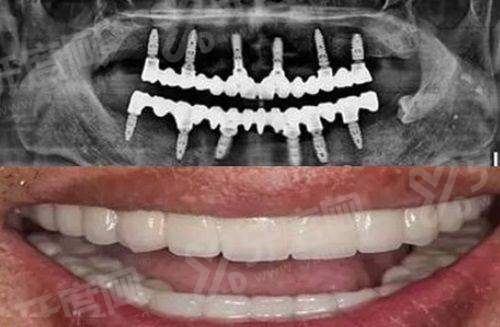

李凤元:主任医师。擅长口腔修复、种植牙、口腔外伤、口腔肿瘤等疾病。